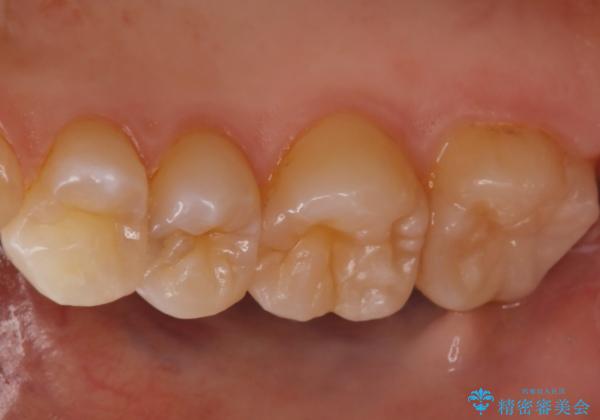

- 他院にて虫歯を指摘され、セカンドオピニオンを希望し当院へ来院されました。以前より磨きずらさと舌感の悪さは自覚していたそうです。清掃性、機能性に優れたセラミックインレーにて治療をすることとなりました。

レントゲンから昔詰めた保険の詰め物が入っていることが確認できました。詰め物と歯の隙間が虫歯になっていたためしっかり取り除き、適合の良いセラミックインレーを入れました。